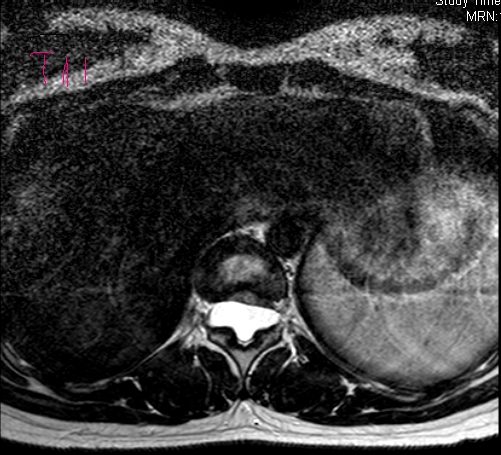

主诉:双下肢乏力4年,加重半年。 病史:患者于4年前无明显诱因出现双下肢乏力,双手支撑地面才能下蹲,无行走困难,无腰部酸痛,无双下肢疼痛、麻木感,大小二便未见异常。半年前,患者诉双下肢乏力及蹲下困难加重,难以下蹲及上下楼梯,无双下肢疼痛、麻木感,大小二便未见异常。遂至外院行MR检查提示:T11-L3水平椎管内蛛网膜囊肿,并相应脊髓圆锥、马尾神经受压移位、聚集。患者一般情况尚可。

查体:双侧踝关节呈跖屈位。腰3/4棘突有轻压痛。右踇背伸肌3-级,左踇背伸肌4级,右踝背屈肌3级,左踝背屈肌4级,右股四头肌2级,左股四头肌3级。右侧膝反射未引出(-),左侧膝反射(+),右侧踝反射(+),左侧踝反射(++),双侧踝阵挛、Babinski征(-)。双侧股神经牵拉(反Lasegue)(+),左侧4字征(+)。

诊断:胸腰椎管内占位待查 治疗:入院后尽快完善相关检查,初步明确胸腰椎管内占位原因,初步评估患者病情及是否可进行手术。经治疗组讨论后,拟后路蛛网膜囊肿切除+栓系松解+钉棒内固定术”,术后根据病理决定是否进行下一步治疗。